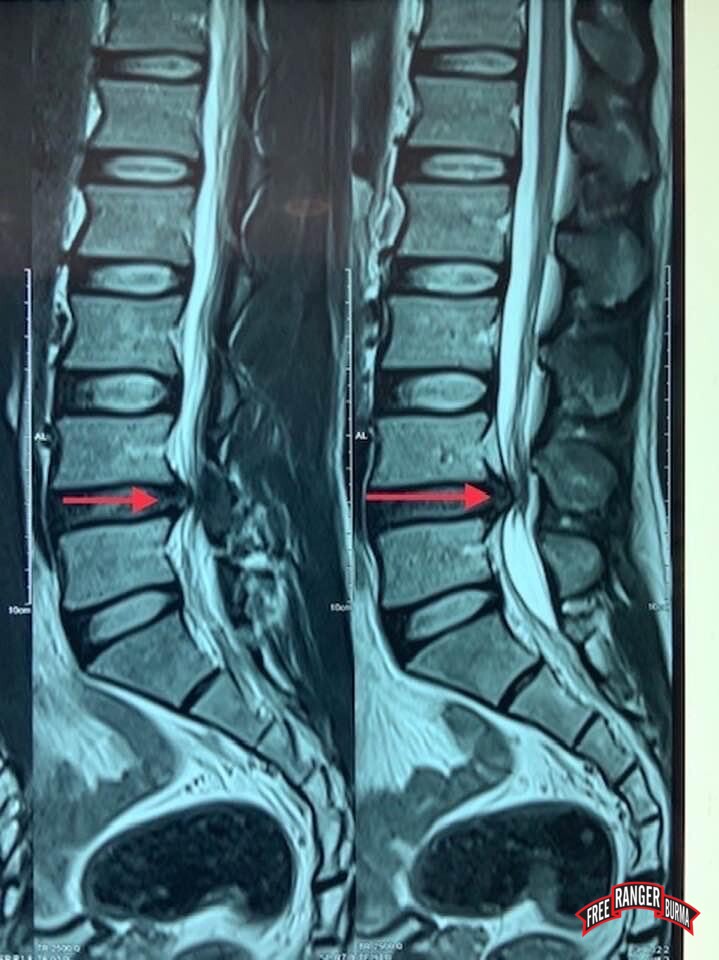

A few months later, Silverhorn's lumbar nerve impingement condition, which had been chronic even before his battlefield injury, began progressing to a point he was unable to walk without much pain. The medical treatment was lengthy and complex as he still had shrapnel lodged into his back from his earlier injury. With the help of God, FBR's patient care team, supporting medical staff, and donors around the world, Silverhorn received a successful surgery and recovery in June 2023. We are happy to report that he is now home and reunited with his family.